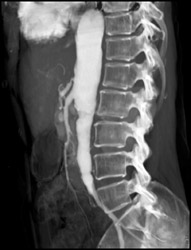

Cavernous Transformation of the Portal Vein (CTPV)